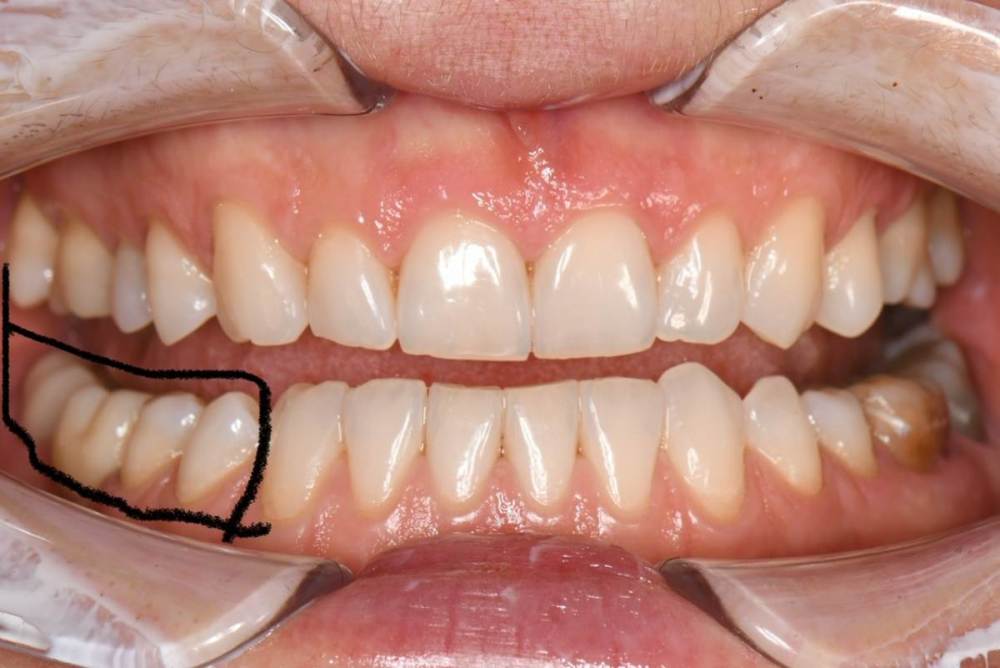

Но врач ортопед  делает низкую коронку , видимо ориентируясь на 47 зуб, не беря в учет , что он не в прикусе. Переделывать отказывается , так я хожу 3 года с низкой коронкой на 46 зубе, так как мне сказали, что это норма и я должна привыкнуть , так как это искуственный зуб , и нормально , что я его не чувствую и он в прикусе. Осенью прошлого года , я все таки решила пойти к другому ортопеду , так как я так и немогла привыкнуть к этой коронке. Выяснилось , что за 3 года использования , я стерла фронт и 5 зуб и клык.  Я решила поменять коронку , но мне опять ее делают низкой . Я прошу изначально , перед слепками и объясняю ортопеду , что мне нужно выше. Но мне говорят , что врачи знают больше пациента и есть протоколы по которым действуют ортопеды , а не руководствуются ощущениями пациента.  Мне ставят коронку вновь . И вновь смыкая левую челюсть , правая у меня в воздухе. Оплачиваю , иду домой. Опять немогу жевать , жутко не удобно и мой пятый зуб задействован больше , чем 46 и 47 .

Высылаю фото отпечатков при прикусе , мою искривленную улыбку  панараму 2016 года до имплантации и сейчас. Так же ситуацию с 36.37

DSC_2179.JPG

DSC_2178.JPG